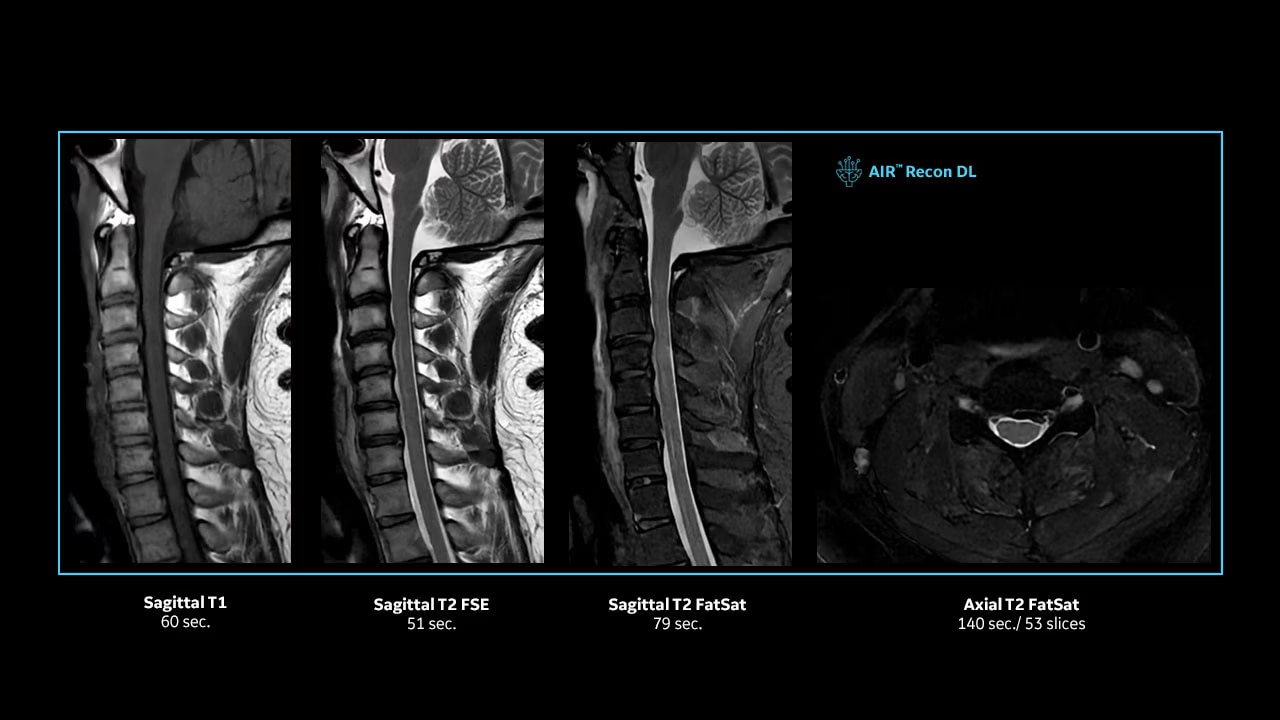

With access to the latest advanced AI technology, you can scan all anatomies and achieve pin-sharp images. Our pioneering deep learning-based reconstruction algorithm AIR Recon DL accelerates scan time and puts patients at ease.

The improved gradient of up to 80 mT/m, 200 T/m/s provides exceptional results faster and with 146 RF channels, you can ensure uniformity for every result.